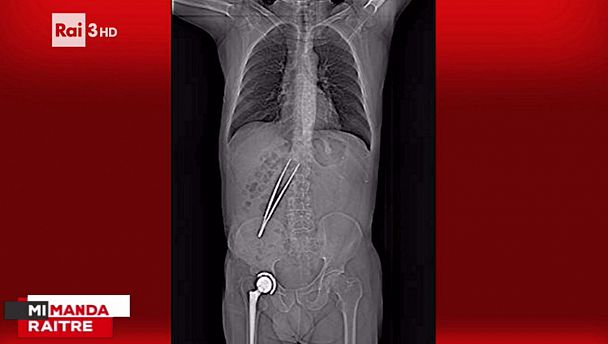

La tac in cui si vede la pinza dimenticata nel corpo di Cellini

I ferri del chirurgo dimenticati nel corpo del paziente. E' quello che è accaduto a Mauro Cellini, 64 anni di Dicomano. L'uomo era stato operato per due volte per un tumore al colon, la prima a novembre 2015, la seconda a luglio. Nella seconda operazione, avvenuta all'ospedale di Careggi, una pinza è stata dimenticata nel suo addome. La pinza è rimasta nel corpo dell'uomo per due mesi e mezzo.

Un errore che sarebbe potuto costare carissimo al paziente. Ad accorgersi dell'oggetto dimenticato un altro medico che stava controllando una tac fatta qualche tempo dopo e dove la pinza era ben visibile.